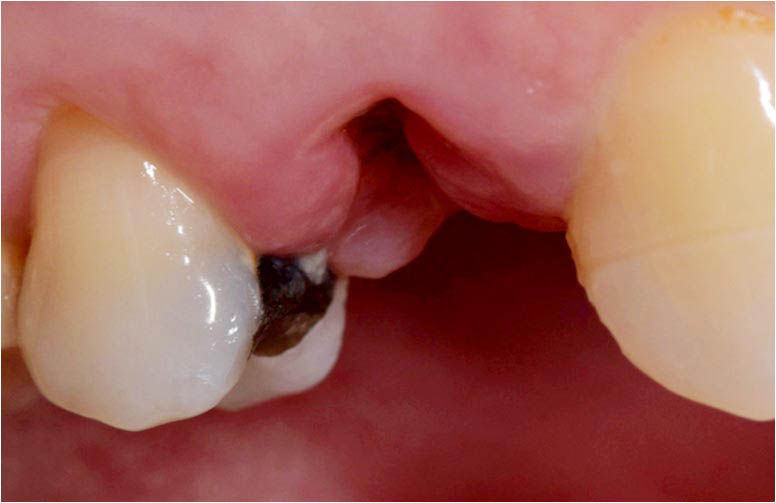

Initial clinical case.

Clinical picture and radiograph of the implant in situ with the healing screw inserted.